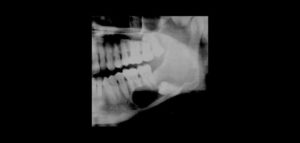

Paciente femenino de 34 años es referido al Instituto de Diagnóstico Maxilofacial para seguimiento de lesión en mandíbula. Se muestra la radiografía panorámica inicial (Figura